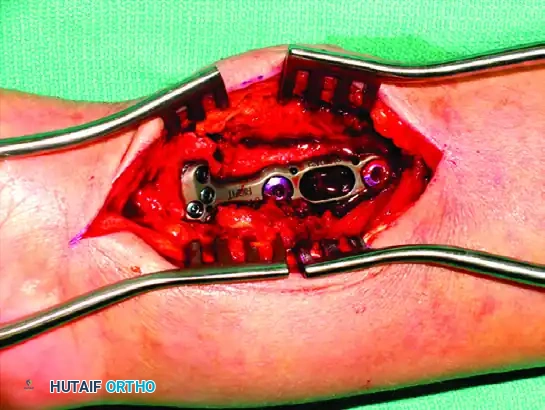

Recognizing the biomechanical pitfalls of isolated Kirschner wire fixation and standard plate-and-screw constructs—especially when dealing with highly comminuted intra-articular fractures in osteopenic bone—Medoff developed a comprehensive wrist fixation system. This system (commercialized as the TriMed system) combines the principles of pinning and plating to achieve stable, fragment-specific reconstruction of the distal radius.

Thin metaphyseal cortical bone does not hold standard screws well. Furthermore, conventional thick plates cannot be applied easily to the dorsal aspect of the distal radius due to the high risk of extensor tendon irritation and eventual rupture. Fragment-specific fixation utilizes low-profile wire-forms and pin-plates to capture these specific fragments without adding excessive bulk.

By adding a small buttress plate to the radial styloid pin, the construct is transformed. The pin-plate provides two distinct fixation points: the first through the distal end of the plate, and the second through the intact medial radial cortex. This dual-point constraint prevents collapse, resists dorsal torque, and halts radial migration.

Fragment-Specific Implants and Application

1. The Radial Pin-Plate:

Applied to the radial column, this implant enhances stability by providing a radial buttress. It effectively neutralizes bending forces that would otherwise cause the radial styloid to displace proximally and radially.

2. The Ulnar Pin-Plate:

The dorsal ulnar fragment (often involving the sigmoid notch) is stabilized with an ulnar pin-plate. By proper contouring, this plate can close gaps in the sagittal plane,

Associated Surgical & Radiographic Imaging